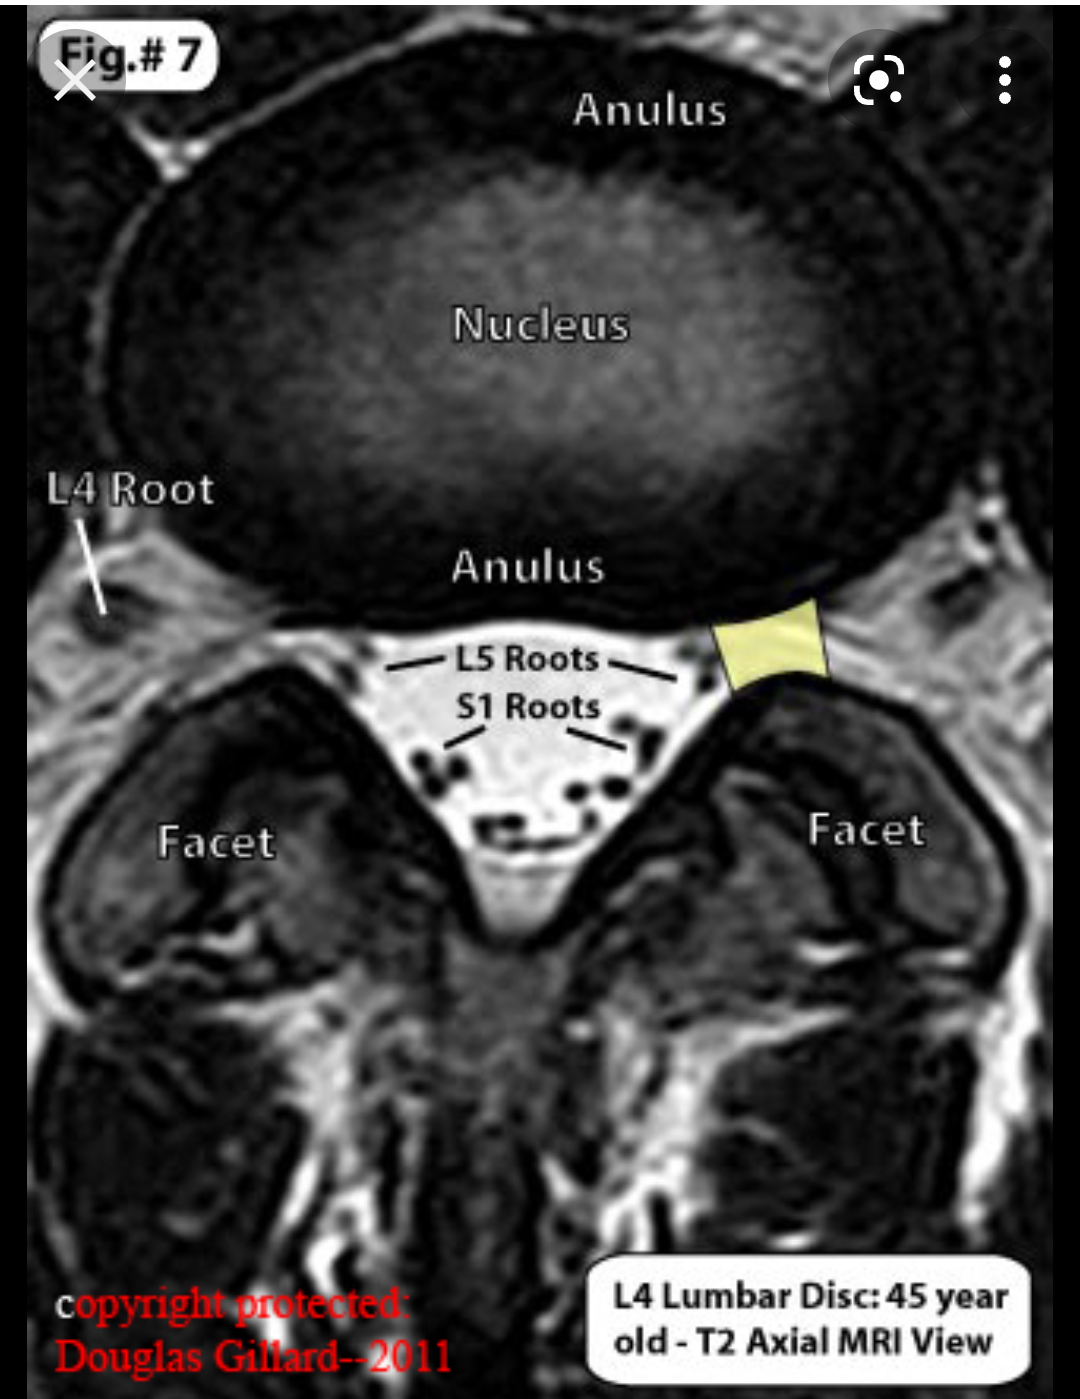

Лечението на дискова херния може да бъде консервативно или хирургично. В консервативното лечение се използват нестероидни противовъзпалителни лекарства, аналгетици, физиотерапия, балнеолечение, ЛФК и други. Хирургичното лечение се налага в случаи на тежки увреждания или когато консервативните методи не доведат до подобрение. Алтернативните лечебни методи за дискова херния включват остеопатия, боуен терапия, хомеопатия, озонна нуклеолиза и други алтернативни терапии, които се различават от традиционните медицински подходи. Основните методи за лечение на дискова херния включват първична терапия с противовъзпалителни лекарства, почивка, подходящи упражнения, физиотерапия, кинезитерапия, ергономични столове и правилна стойка при седене. В някои случаи може да са необходими хирургични интервенции. Различните лечебни методи за дискова херния включват физиотерапия, масажи, балнеолечение и упражнения. Тези методи могат да се използват преди и след операция. Освен това е важно да се консултират с неврохирург и ортопед за персонализиран подход към лечението.